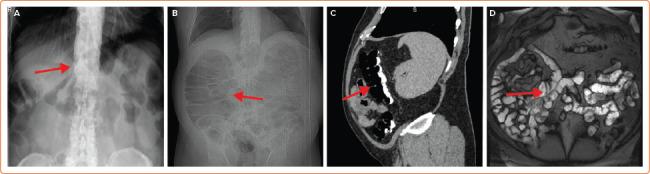

Injury to structures adjacent to the heart, particularly oesophageal injury, accounts for a large proportion of fatal and life-altering complications of ablation for persistent AF. Avoiding these complications dictates many aspects of the way ablation is performed. Because avoidance involves limiting energy delivery in areas of interest, fear of extracardiac injury can impede the ability of the operator to perform an effective procedure. New techniques are becoming available that may permit the operator to circumvent this dilemma and deliver effective ablation with less risk to adjacent structures. The authors review all methods available to avoid injury to extracardiac structures to put these developments in context.

心脏邻近结构的损伤,尤其是食管损伤,在持续性房颤消融的致命和改变生活的并发症中占很大比例。避免这些并发症决定了消融手术的许多方面。由于避免措施涉及限制在感兴趣区域的能量传递,对心外损伤的担忧可能会妨碍操作者进行有效手术的能力。新的技术正在出现,这可能使操作者能够规避这一困境,并在降低对邻近结构风险的情况下进行有效的消融。作者回顾了所有可用于避免心外结构损伤的方法,以便将这些进展置于相应背景中。